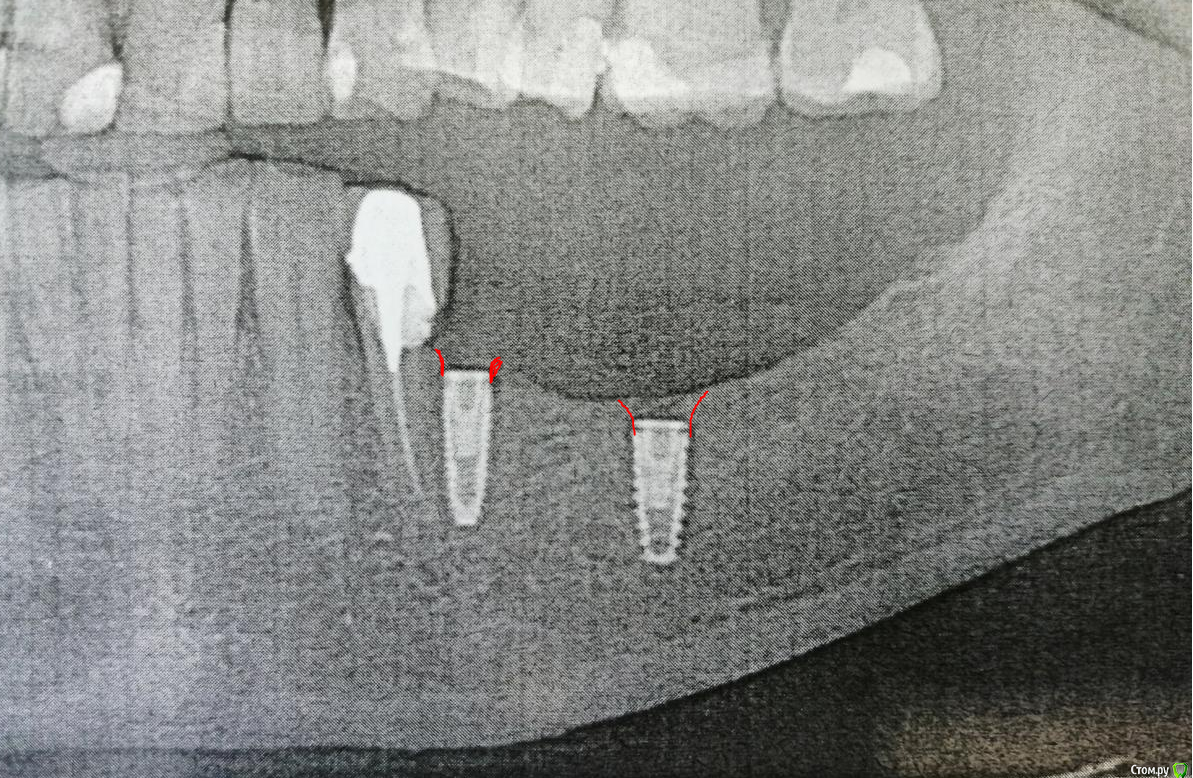

red_butler Опубликовано 18 октября, 2018 Поделиться Опубликовано 18 октября, 2018 Не знаю что за система, но обе заглушки не докручены, и если хирург не сформирует контур, то проблемы начнутся ещё на этапе слепков. 1 Ссылка на комментарий

Eddie Опубликовано 19 октября, 2018 Поделиться Опубликовано 19 октября, 2018 Не знаю что за система, но обе заглушки не докручены, и если хирург не сформирует контур, то проблемы начнутся ещё на этапе слепков.Подскажите по контуру. Кость убрать таким образом? Ссылка на комментарий

EEcho Опубликовано 19 октября, 2018 Поделиться Опубликовано 19 октября, 2018 У некоторых систем есть фрезы для формирования костной манжетки. 1 Ссылка на комментарий

red_butler Опубликовано 19 октября, 2018 Поделиться Опубликовано 19 октября, 2018 Подскажите по контуру. Кость убрать таким образом?я бы больше снимал 1 Ссылка на комментарий

Pavel-Pskov Опубликовано 19 октября, 2018 Поделиться Опубликовано 19 октября, 2018 Если они с переключением, мб и норм. Ссылка на комментарий